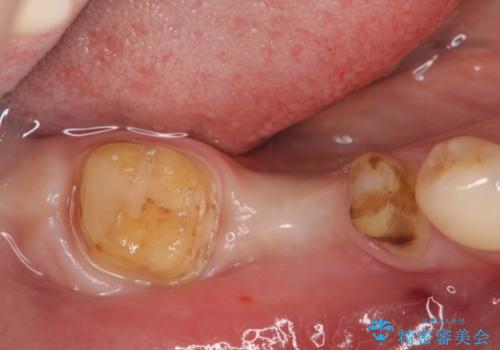

- 虫歯で歯を失い、インプラント治療を希望され来院されました。

吸収した骨を造骨にて補い、インプラントによる機能回復を計画します。

歯を失ってからの時間が経過し骨が吸収してしまっていても、造骨を行うことで予知性の高いインプラント治療を行うことができます。